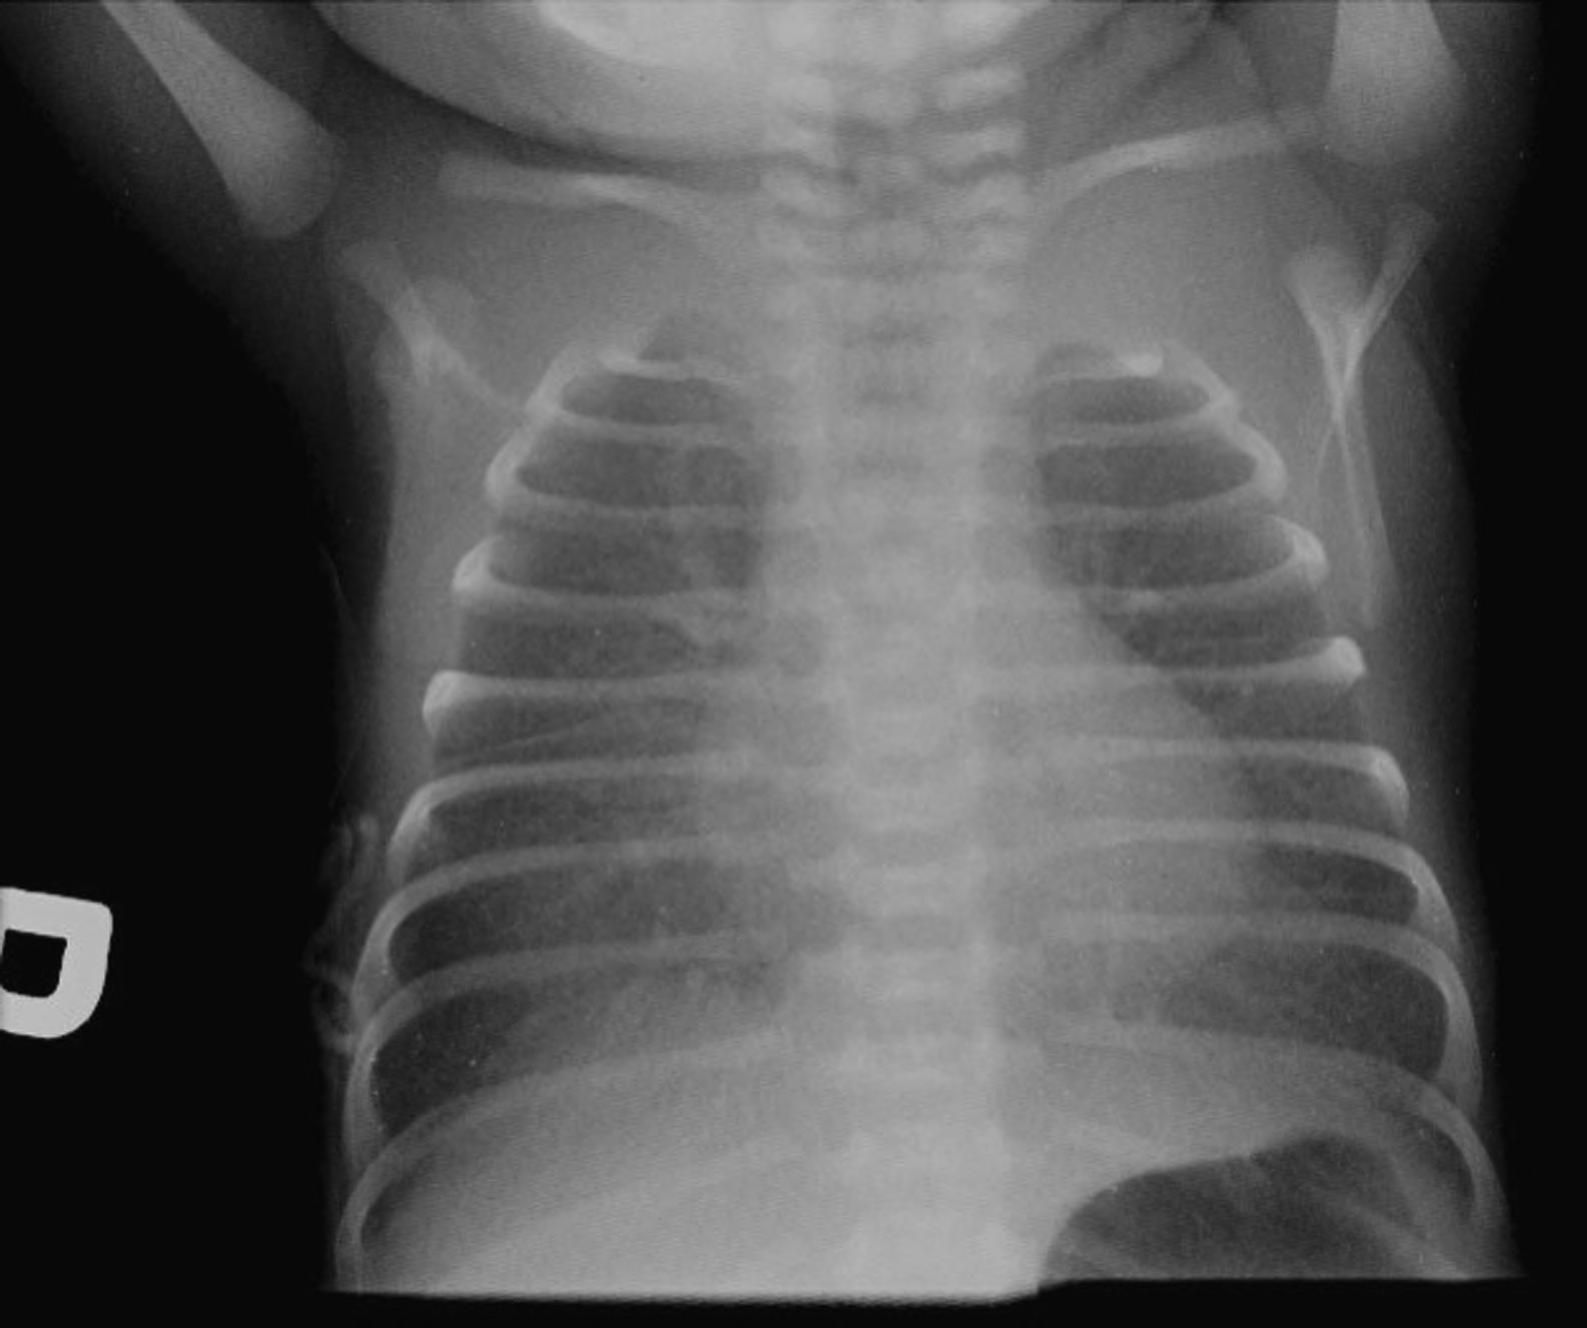

The clinicians for this patient started with a chest radiograph. The initial chest radiographic identified small pleural effusions and interlobular septal thickening, which were suggestive of interstitial pulmonary edema (see Figures 1.1a and 1.1b). Findings become more apparent when compared with a normal 16-year-old’s chest radiographs (Figures 1.2a and 1.2b). Because of the patient’s vomiting, an abdominal film was also obtained, which demonstrated significant cardiomegaly (see Figure 1.1c), thus leading to the diagnosis of dilated cardiomyopathy and/or pericardial effusion. On the chest radiograph, the reduced lung volumes and elevated hemidiaphragms masked the cardiomegaly, which was more apparent on the better penetrated abdominal radiograph.

FIGURES 1.1 a, 1.1b, 1.1c, AND 1.1d . (a, b) PA and lateral views of the chest demonstrating low lung volumes, pulmonary vascular congestion, interstitial opacities in the lung bases, and bilateral trace pleural fluid; (c) the abdominal radiograph is better penetrated than the chest radiograph, and shows an enlarged cardiac silhouette; and (d) post-procedure chest radiograph showing decreased size of the cardiac silhouette after drainage of the pericardial effusion.

FIGURES 1.2 a AND 1.2 b PA and lateral views of the chest in a normal 16-year-old for comparison (different patient). Note the normal appearance of structures. Contour of descending aorta (white arrowheads), superior mediastinal width between superior vena cava on the right and aortic arch on the left (white thick arrows on right and left side), tracheal air column (black arrow), carina (black arrowhead), and the orientation of the clavicles (thin white arrows). In a properly positioned patient the spinous processes lie midway between the medial ends of the clavicles. The cardiothoracic ratio is measured as the ratio of the cardiac transverse diameter (black thin line) divided by the maximum chest transverse diameter (thick black line). The first and second ribs on the left side are numbered (1, 2).